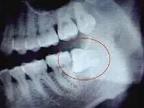

4.去骨

去除全部牙合面和部分頰側(cè)、遠(yuǎn)中的牙槽骨。一般原則:顯露牙冠最大周徑;盡量保持頰側(cè)皮質(zhì)骨高度;根據(jù)拔除難度及切割牙冠方式確定去骨量。為保持牙槽骨高度,頰側(cè)及遠(yuǎn)中去骨時(shí)可僅磨除貼近患牙的部分。為保護(hù)舌神經(jīng)、第二磨牙及其牙周骨質(zhì),原則上不去除舌側(cè)及近中牙槽骨,遠(yuǎn)中不超中線,將分離器置于遠(yuǎn)中骨板周?chē)M(jìn)行保護(hù)。

去骨時(shí)先確定最小的去骨量,一般垂直阻生去骨或增隙須達(dá)牙冠外形高點(diǎn)以下;水平和近中阻生應(yīng)達(dá)近中頰溝之下,以便分切牙冠;遠(yuǎn)中阻生至遠(yuǎn)中牙頸部以下,以便消除遠(yuǎn)中阻力。